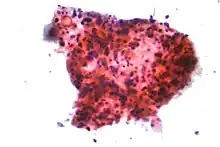

Lung cancers are classified according to histological type.[12] This classification is important for determining both the management and predicting outcomes of the disease. Lung cancers are carcinomas – malignancies that arise from epithelial cells. Lung carcinomas are categorized by the size and appearance of the malignant cells seen by a histopathologist under a microscope. For therapeutic purposes, two broad classes are distinguished: non-small-cell lung carcinoma and small-cell lung carcinoma.[69]

_by_core_needle_biopsy.jpg)

In SCLC, the cells contain dense neurosecretory granules (vesicles containing neuroendocrine hormones), which give this tumor an endocrine or paraneoplastic syndrome association.[74] Most cases arise in the larger airways (primary and secondary bronchi).[13] Sixty to seventy percent have extensive disease (which cannot be targeted within a single radiation therapy field) at presentation.[2]